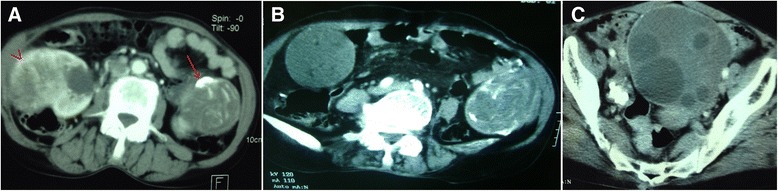

Figure 2.

Tomodensitometric scans show renal tumor as well as abdominal and pelvic cystic formations. In addition to renal tumor (A, arrow), tomodensitometric scans reveal abdominal (A, arrow; B) and pelvic (C) cystic formations, some of which are calcified.